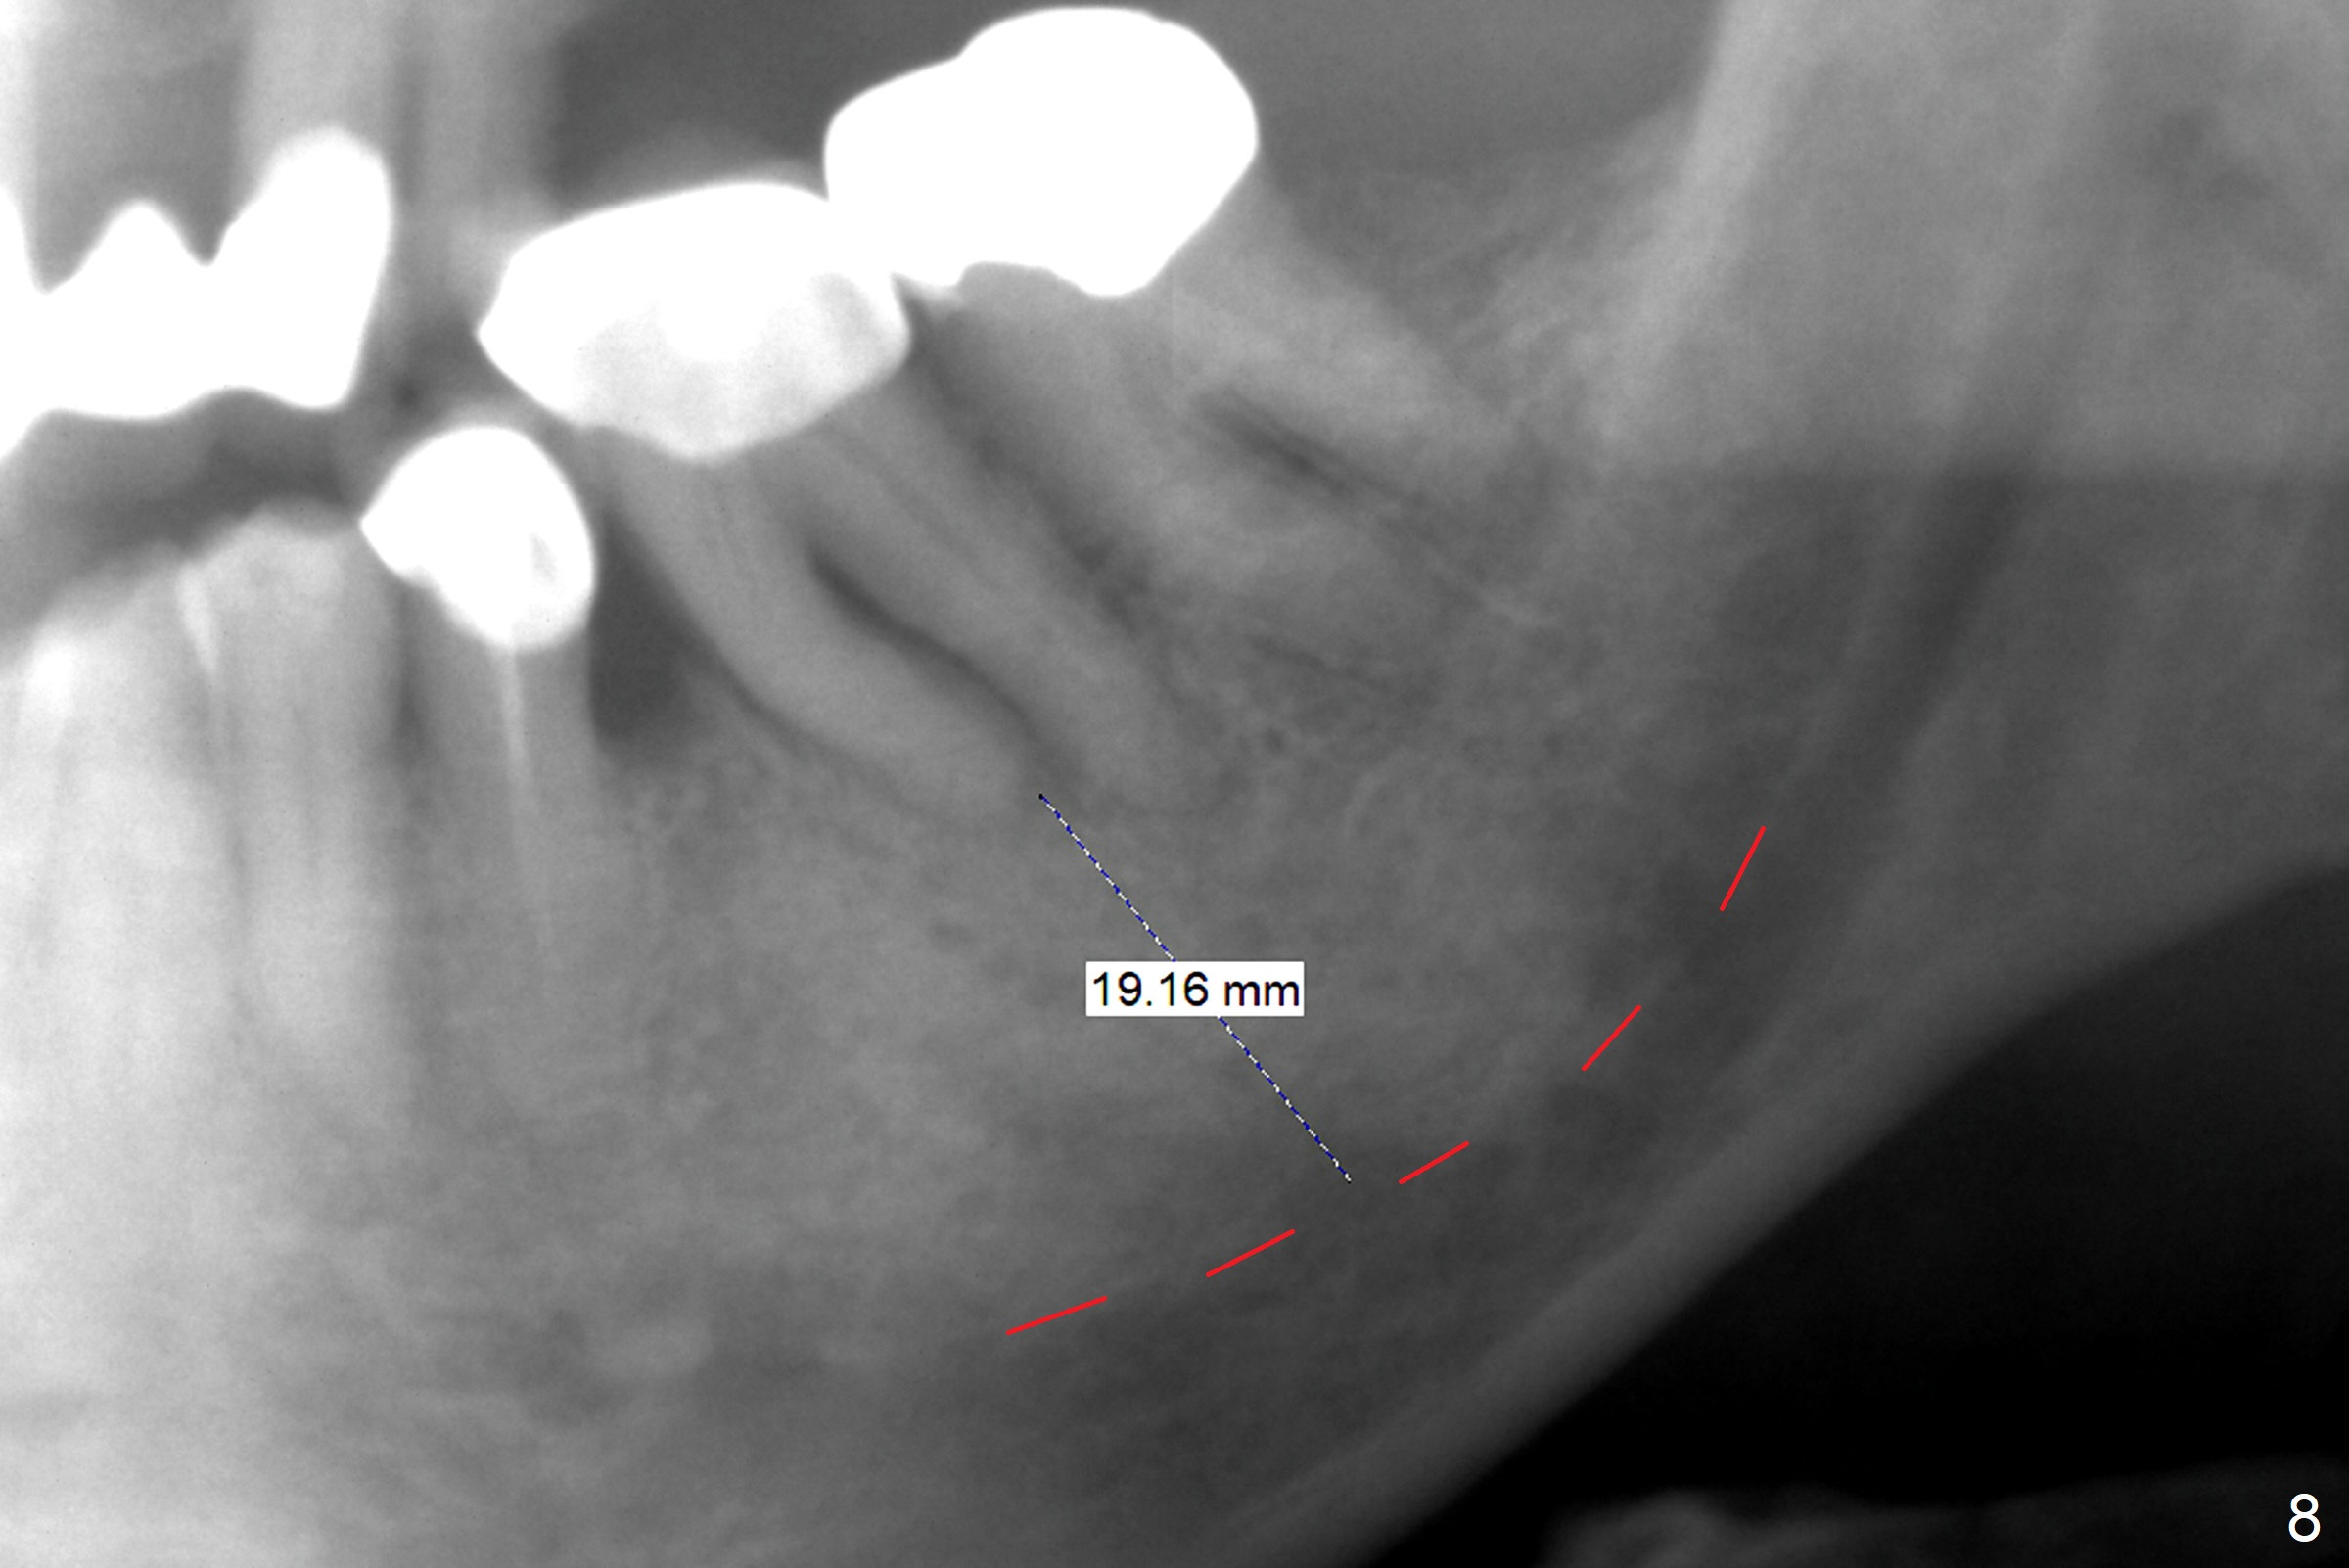

After extraction of the supraerupted tooth #19 with severe buccal gingival recession, the buccal and lingual plate are found to be lost. The sockets are fused and flat without the septum. The bone is hard and painful for the initial osteotomy with infiltration anesthesia (Fig.2). Following block anesthesia, the initial osteotomy depth extends to 8 mm (Fig.3,4). With apparent 4.9 mm clearance, the osteotomy is further extended to 10 mm. The osteotomy walls are apparently intact without severe hemorrhage after each drill. Due to the thick gingiva and severe bone loss, a 5x12 mm implant is intentionally placed 3 mm above the base of the socket bone (Fig.5,6 (yellow dashed line)). Vanilla Cortical and Cancellous allograft (Fig.6 *) is placed around the exposed implant and 7.8x5(6) mm abutment with 4 and 2 mm buccal and lingual gaps. Next collagen plug cut in strip is placed to fill the most coronal aspect of the socket (Fig.7 *). The buccal and lingual gingivae are approximated with sutures proximally. Finally periodontal dressing is applied. Since the Inferior Alveolar Canal is vague in intraop PAs (Fig.4,5), there is worry about potential nerve damage during and after osteotomy. This should be no issue if preop panoramic X-ray is reviewed with measurement (Fig.8). The bone graft appears to remain in place nearly 4 months postop (Fig.9). Two weeks later, he returns for impression. When the provisional is removed, the gingiva is unhealthy. Without the provisional and with improved oral hygiene, the gingiva is healthy one week later, but the tooth #18 is symptomatic. The latter is extracted with socket preservation (Fig.10 *). There is no apparent bone loss around the implant at #19 6.5 months post cementation (Fig.11).